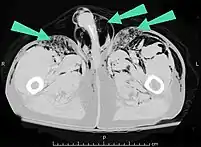

| An abdominal CT scan of a patient with subcutaneous emphysema (arrows) | |

Significant cases of subcutaneous emphysema are easy to diagnose because of the characteristic signs of the condition.[1] In some cases, the signs are subtle, making diagnosis more difficult.[13] Medical imaging is used to diagnose the condition or confirm a diagnosis made using clinical signs. On a chest radiograph, subcutaneous emphysema may be seen as radiolucent striations in the pattern expected from the pectoralis major muscle group. Air in the subcutaneous tissues may interfere with radiography of the chest, potentially obscuring serious conditions such as pneumothorax.[18] It can also reduce the effectiveness of chest ultrasound.[27] On the other hand, since subcutaneous emphysema may become apparent in chest X-rays before a pneumothorax does, its presence may be used to infer that of the latter injury.[13] Subcutaneous emphysema can also be seen in CT scans, with the air pockets appearing as dark areas. CT scanning is so sensitive that it commonly makes it possible to find the exact spot from which air is entering the soft tissues.[13] In 1994, M.T. Macklin and C.C. Macklin published further insights into the pathophysiology of spontaneous Macklin's Syndrome occurring from a severe asthmatic attack.